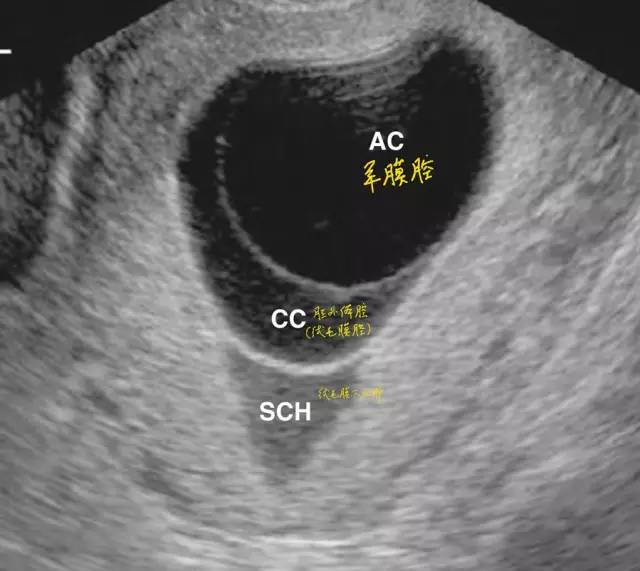

绒毛膜下血肿超声表现 羊膜